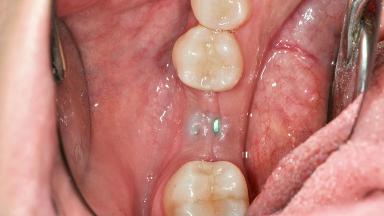

Adequate peri-implant soft-tissue thickness is essential not only for esthetic but also for functional reasons. In this case, Vincenzo Iorio Siciliano demonstrates how he achieved increased height and thickness of posterior peri-implant soft tissues to obtain a stable mucosal seal and a width of keratinized tissue favorable to toothbrushing.

The patient, a healthy 38-year-old woman, was referred for increasing the width of the keratinized tissues at the buccal aspect of dental implant 46. The site exhibited a premature-closure screw exposure caused by trauma during chewing, with inadequate keratinized tissue.